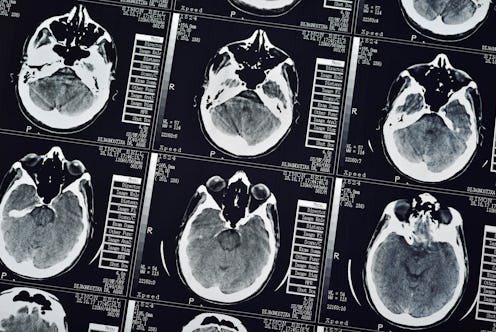

As the human brain ages, it’s normal to experience a decline in brain metabolism, changing how the brain burns energy. By evaluating the brain imaging scans of 205 cognitively “normal” adults, ranging from 20 to 82 years old, the researchers studied how sugar was being metabolized into energy across varying parts of the participants’ brains, determining the subjects’ “metabolic brain age.” For example, if a brain scan showed a person with a lower brain metabolism, they would be predicted as having an older metabolic brain age.

In the study, published in Proceedings of the National Academy of Sciences, a computer algorithm predicted participants’ ages based on brain metabolism depicted in the brain scans. The algorithm was able to predict men’s ages relatively accurately from the male brain scans, but when it came to female brains, it would estimate the women’s brains were on average 3.8 years younger than their actual age. When the researchers inverted the process and first trained the algorithm to predict women’s ages from brain data scan accurately, the male brain scans were predicted on average to be 2.4 years older than the men’s actual ages.